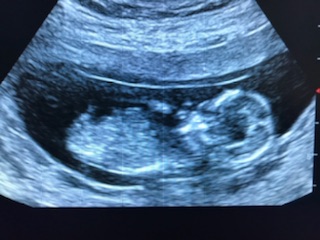

Thanks so much everyone. This is definitely one of the hardest things I have had to go through. We found out today it was probably a precious little girl!❤❤Attachment 39556